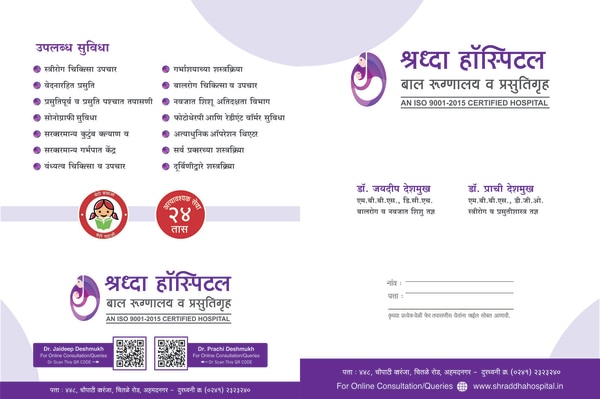

SHRADDHA HOSPITAL . Dr Deshmukh Mother and Child Care Hospital in Ahmednagar. Established in the year 2009, SHRADDHA HOSPITAL Dr Deshmukh Mother and Child Care Hospital in Chitale Road, Ahmednagar is a top player in the category Hospitals in the Ahmednagar. This well-known establishment acts as a one-stop destination servicing customers both local and from other parts of Ahmednagar. Over the course of its journey, this business has established a firm foothold in it’s industry. The belief that customer satisfaction is as important as their products and services, have helped this establishment garner a vast base of customers, which continues to grow by the day. This business employs indiv...